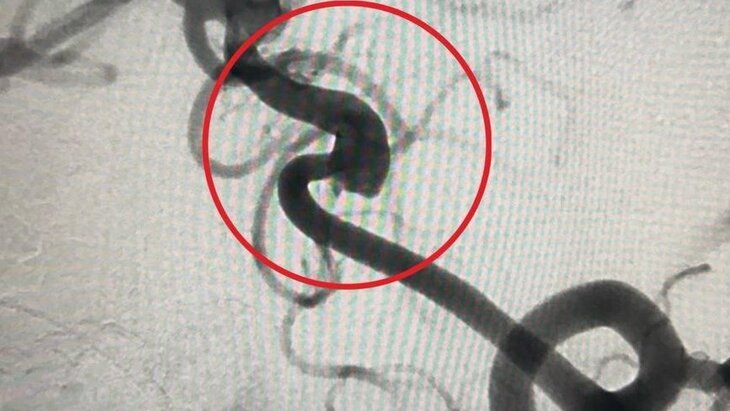

Специалисты Детского клинического центра имени Рошаля оказали помощь юному пациенту, который поступил в медучреждение с редкой аневризмой в сосудах головного мозга. Об этом сообщили в пресс-службе Минздрава Подмосковья.

По информации ведомства, врачи диагностировали 9-летнему мальчику аномальное расширение стенки ствола основной артерии, отвечающей за кровоснабжение органа центральной нервной системы. Выявленная патология могла стать причиной инсульта или кровоизлияния в мозг.

В ходе операции медики провели катетер к сосудам мозга через бедренную артерию и имплантировали поток-перенаправляющий стент, разместив его в области аневризмы. Благодаря успешному вмешательству хирургам удалось предотвратить риск инсульта у пациента.